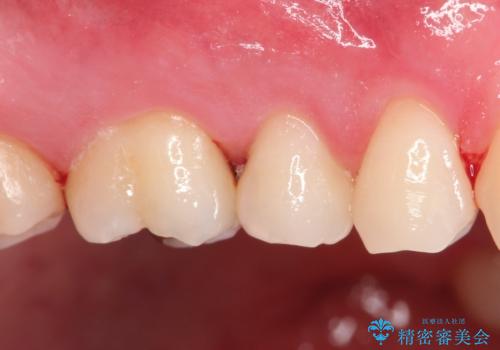

【セラミックインレー】定期検診にて虫歯を発見

- 定期検診にて虫歯を発見したため、セラミッククラウン、セラミックインレーにて治療を行いました。

小臼歯の虫歯は歯髄に近かったため、部分的断髄法にて歯髄を部分的に保存した治療をおこなっています。